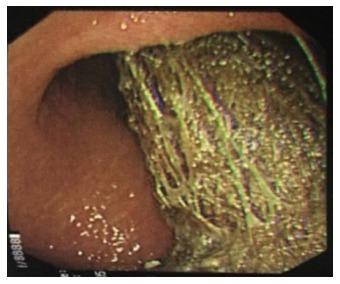

Recurrent Rapunzel syndrome (RRS) is a rare clinical presentation with fewer than six cases reported in the PubMed literature. A report of RRS and literature review is presented. A 25-year-old female was admitted to hospital with a 4-wk history of epigastric pain and swelling. She had a known history of trichophagia with a previous admission for Rapunzel syndrome requiring a laparotomy nine years earlier, aged 16. Psychological treatment had been successfully achieved for nine years with outpatient hypnotherapy sessions only, but she defaulted on her last session due to stressors at home. The abdominal examination demonstrated an epigastric mass. Computer tomography scan revealed a large gastric bezoar and features of aspiration pneumonia. The patient underwent emergency open surgical laparotomy for removal as the bezoar could not be removed endoscopically. The bezoar was cast in a shape that mimicked the contours of the stomach and proximal small bowel, hence the diagnosis of RRS. The patient was seen by a psychiatrist and was commenced on Quetiapine before discharge. She continues to attend follow-up.

复发性长发公主综合征(RRS)是一种罕见的临床表现,在PubMed文献中报道的病例少于6例。本文呈现了一例RRS病例报告及文献综述。一名25岁女性因上腹部疼痛和肿胀4周病史入院。她有吞食毛发的病史,16岁时曾因长发公主综合征入院,9年前需要进行剖腹手术。仅通过门诊催眠治疗成功进行了9年的心理治疗,但由于家庭压力因素,她未能参加最后一次治疗。腹部检查发现上腹部有肿块。计算机断层扫描显示有一个大的胃石以及吸入性肺炎的特征。由于胃石无法通过内镜取出,患者接受了急诊开放性外科剖腹手术以将其取出。胃石的形状模仿了胃和近端小肠的轮廓,因此诊断为RRS。患者在出院前由精神科医生诊治并开始服用喹硫平。她继续接受随访。